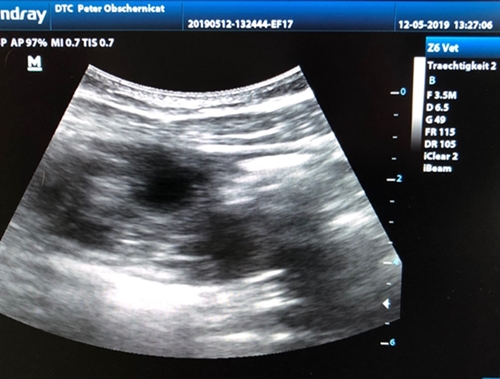

12. Mai 2019

Das perfekte Muttertagsgeschenk

Nyala & Luka werden Eltern

Ich bin unendlich glücklich und dankbar

Nyala´s Date an Gründonnerstag & Karfreitag

mit Luka trägt Früchte. Wenn alles gut geht, kommen

die kleinen Osterhäschen um den 19.06.19 zur Welt.